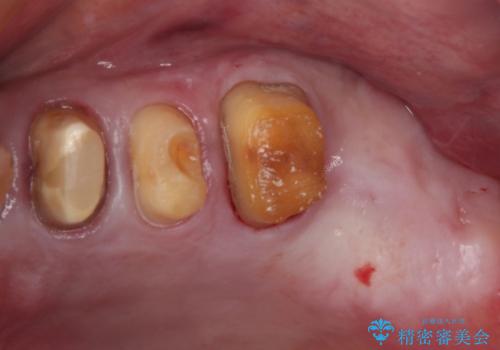

- 奥歯が咬みにくく、前歯がぐらぐらするとのことで来院された患者様です。

咬合力が強く、奥歯が欠損している状態でした。

上顎前歯に歯周ポケットの深い部分がありましたが、インプラントの仮歯で奥歯がしっかりと噛めるようになると、1年程度で深い歯周ポケットは解消されました。